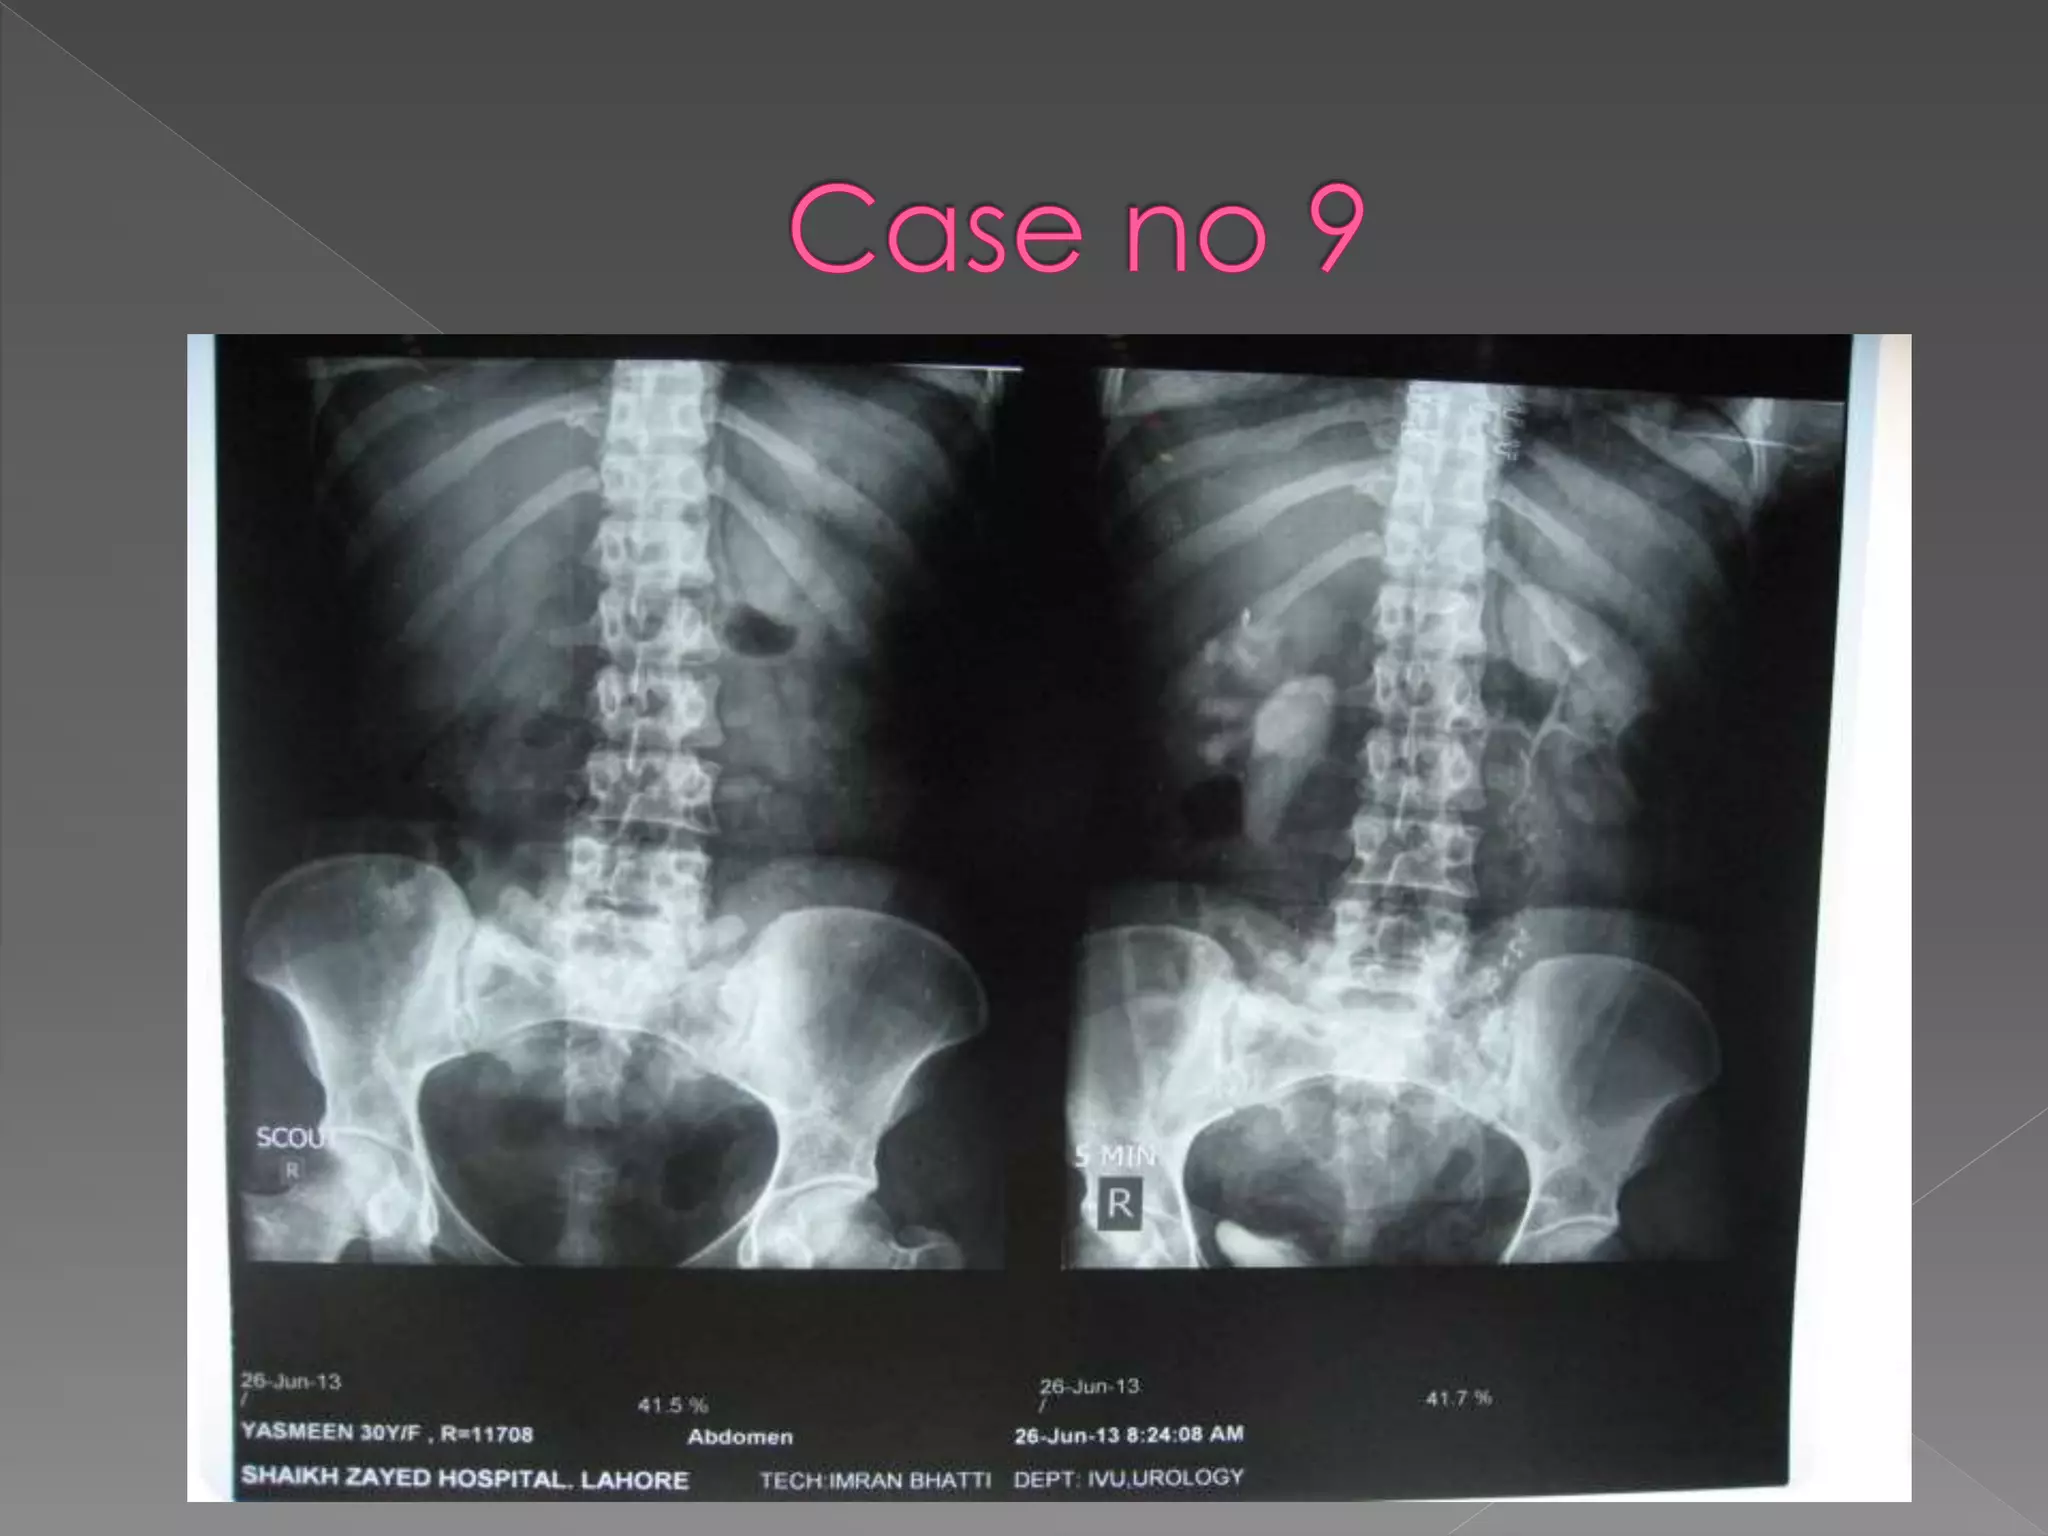

X ray films 1)Pre contrast 2) 5 mins 3) 25 mins 4) Post void